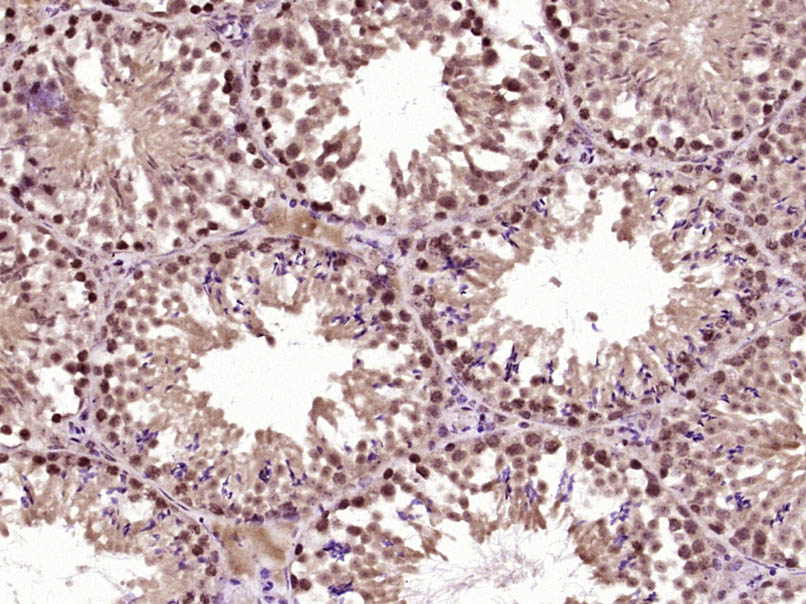

Paraformaldehyde-fixed, paraffin embedded (Mouse testis); Antigen retrieval by boiling in sodium citrate buffer (pH6.0) for 15min; Block endogenous peroxidase by 3% hydrogen peroxide for 20 minutes; Blocking buffer (normal goat serum) at 37°C for 30min; Antibody incubation with (OAS2) Polyclonal Antibody, Unconjugated (bs-15588R) at 1:400 overnight at 4°C, followed by operating according to SP Kit(Rabbit) (sp-0023) instructionsand DAB staining.